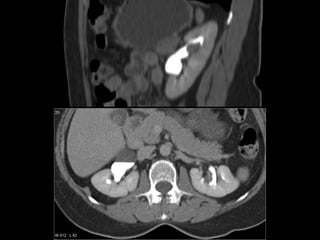

Estudio de Elección:   TC Trifásica Renal  Sin contraste, contraste en fs. arterial, portal y tardía Informa: Comportamiento, tamaño, extensión, número, calcificaciones. Etapificación : compromiso suprarrenal extensión directa a órganos adyacentes adenopatías retroperitoneales invasión de la vena renal y VCI metástasis a distancia (hígado, huesos, cerebro)